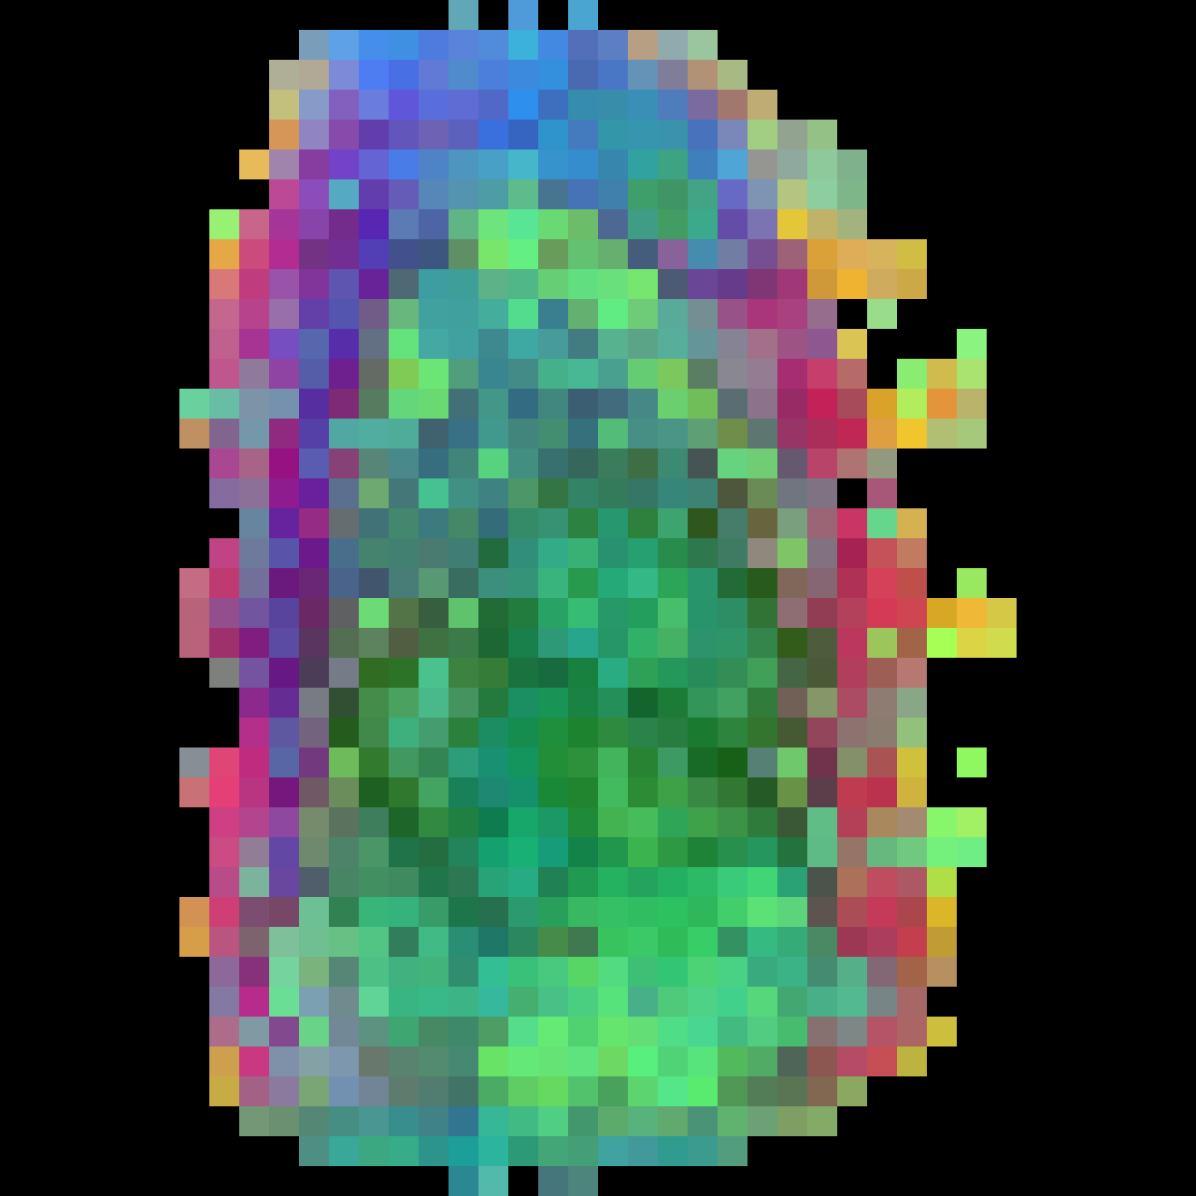

In this section we will show qualitative results of DINOv2 features using principal component analysis (PCA) performed on DINOv2 patch features on X-ray, CT, and MRI scans, following the method delineated in [8]. We will also provide organ segmentation results of linear compared U-Net decoders.

PCA visualization. Figure 2 shows the first three PCA components. The PCA is computed between patches of images that are in the same column, and the first 3 components are shown for X-ray, CT, and MRI scans. Thresholding is used on the first PCA component to remove the background. Just like in natural images [8], the colors of the three PCA components correspond well with the same parts of images in the same category. This is an easier task however, compared to natural images, because there is less variability between examinations on medical images compared to natural images.